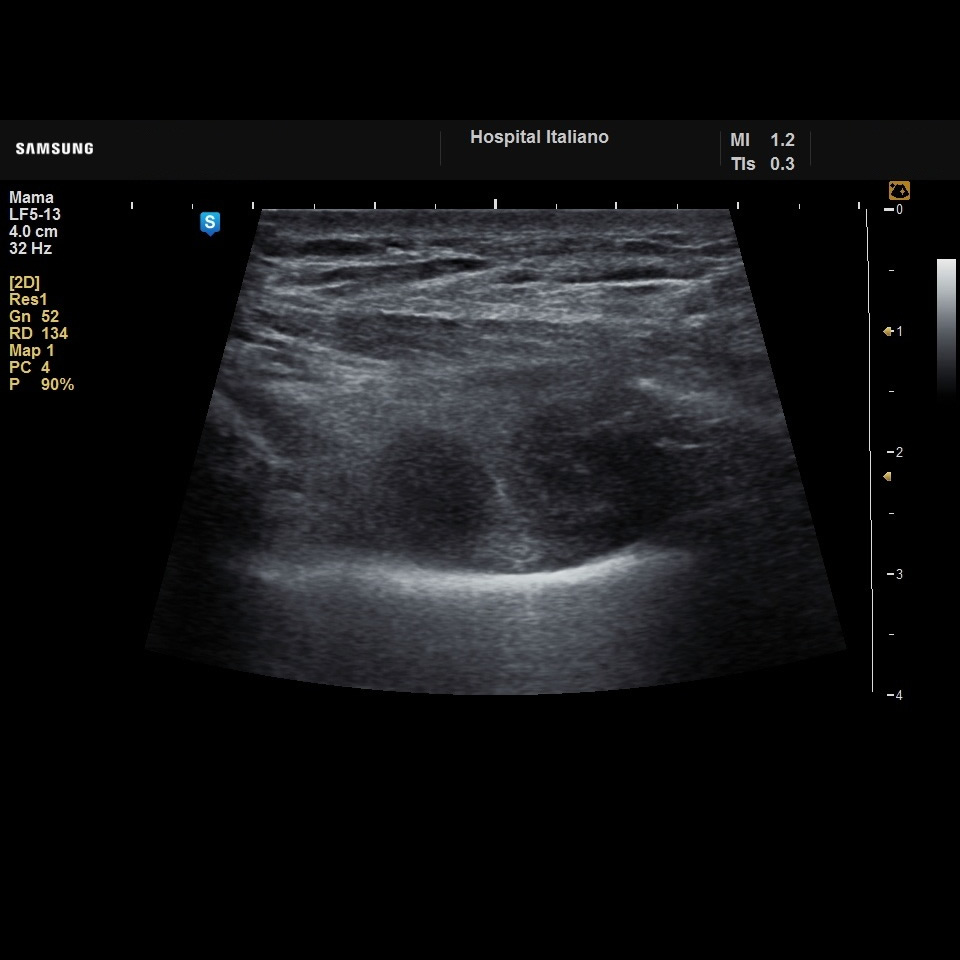

Femenina 64 años

Motivo de Consulta: Tos y equivalentes febriles